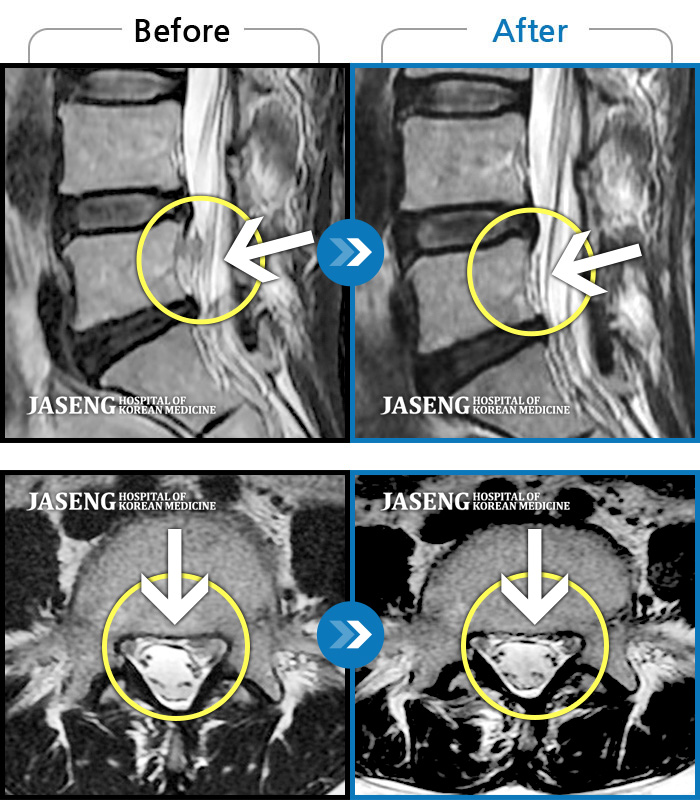

[뱸] 19.11.28~25.05.06

ȯںп Ǹ ǿ ԿǾ, ο ġ ۿ Ƿ ġḦ Ͻñ ٶϴ.